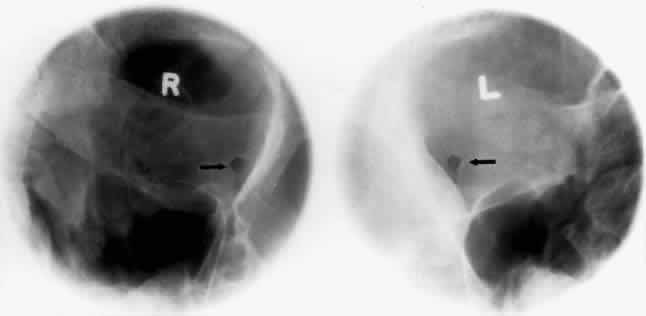

The optic foramen should measure 6 mm vertically and 5 mm horizontally. Asymmetry greater than 1 mm or a vertical dimension greater than 6.5 mm is considered abnormal.15,27 Ninety-eight percent of patients have optic canals that vary by less than 1 mm.27 Concentric enlargement of the foramen and optic canal can be seen with optic nerve gliomas, meningiomas, neurofibromatosis, and less commonly an aneurysm of the ophthalmic artery (Fig. 16). A decrease in the optic foramen and canal dimension can be seen in fibrous dysplasia, Paget's disease, hyperostosis secondary to a meningioma, or microphthalmos (Fig. 17, Table 1).

Fig. 17. Bilateral optic canal compression from fibrous dysplasia. There is diffuse bone thickening in each orbit. Note small size of optic foramen (arrow).